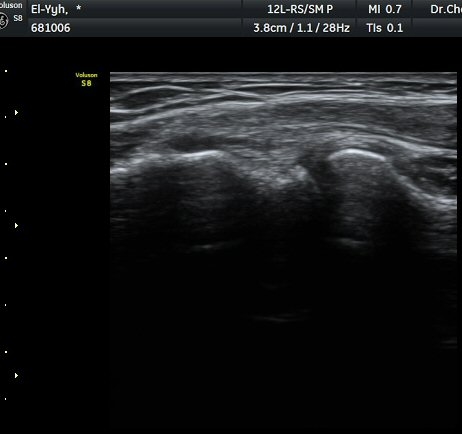

ÃÊÀ½ÆÄ °Ë»ç